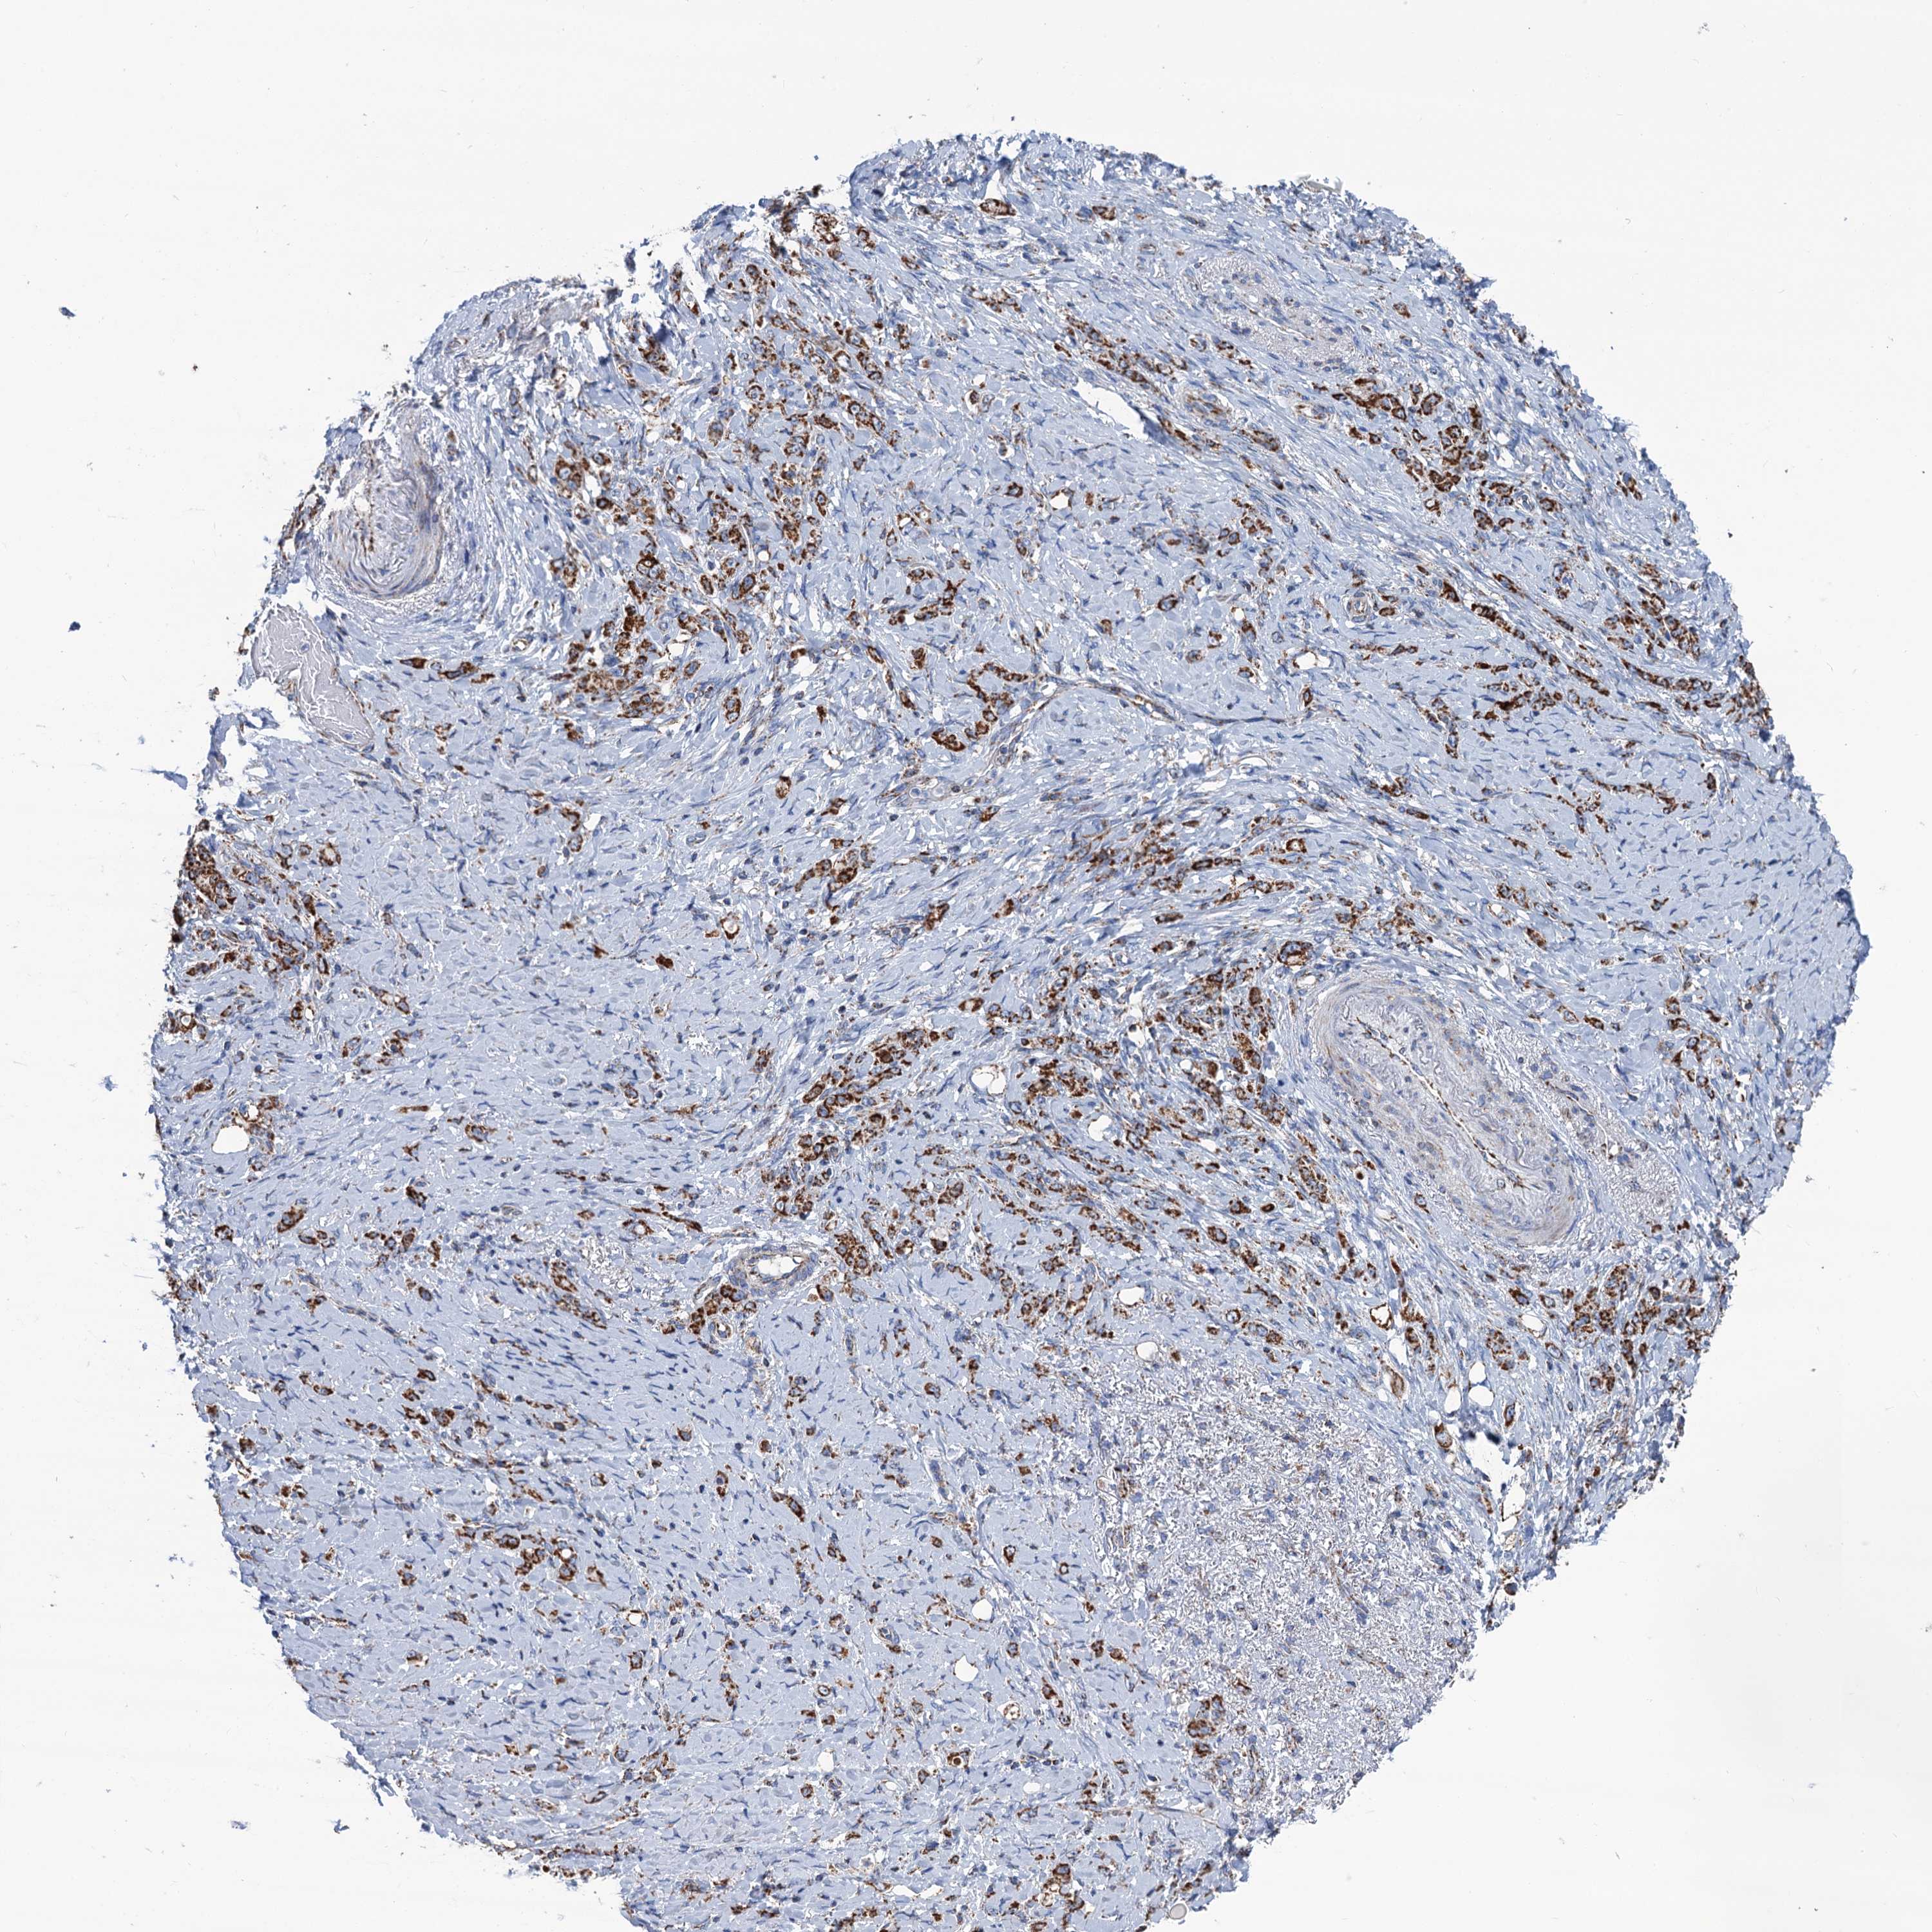

STOMACH CANCER - Protein expressioni

A mouse-over function shows sample information and annotation data. Click on an image to view it in a full screen mode. Samples can be filtered based on level of antibody staining by selecting one or several of the following categories: high, medium, low and not detected. The assay and annotation is described here.

Note that samples used for immunohistochemistry by the Human Protein Atlas do not correspond to samples in the TCGA dataset.

Antibody stainingi

Antibody staining in the annotated cell types in the current human tissue is reported as not detected, low, medium, or high, based on conventional immunohistochemistry profiling in selected tissues. This score is based on the combination of the staining intensity and fraction of stained cells.

Each image is clickable and will lead to virtual microscopy that enables deeper exploration of all samples and also displays staining intensity scores, fraction scores and subcellular localization as well as patient and tissue information for each sample.

Antibody HPA041391

Antibody HPA044250

Staining

High

Medium

Low

Not detected

Intensity

Strong

Moderate

Weak

Negative

Quantity

>75%

75%-25%

<25%

None

Location

Nuclear

Cytoplasmic/membranous

Cytoplasmic/membranous,nuclear

Adenocarcinoma, NOS

Adenocarcinoma, High grade